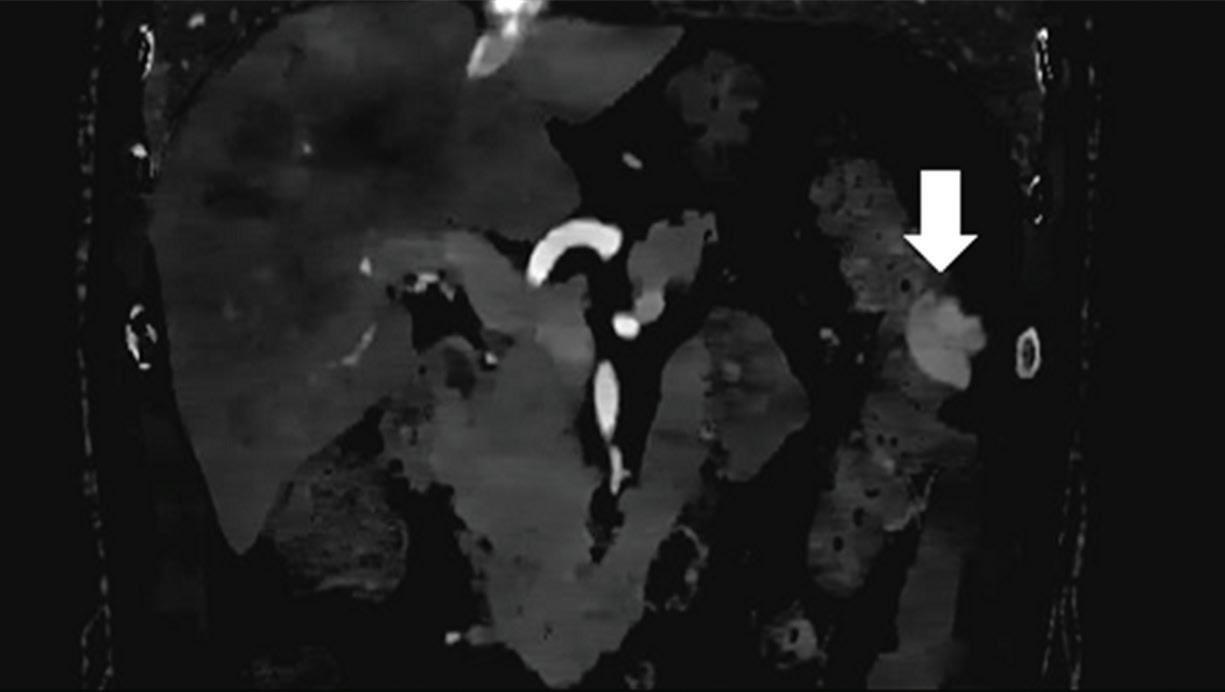

Renal and adrenal gland tumors. Contrast-enhanced-DECT images are particularly useful for the characterization of incidental renal or supra-renal lesions and for their follow-up, without the need of conventional unenhanced acquisition, translating into achieving a 30% mean dose savings for triphasic and up to 50% for biphasic renal protocols in daily clinical practice.17 It is also very useful in depicting hypervascular renal cell carcinoma metastasis in the liver or other sites, such as in the peritoneum and bowel wall (Figures 2 and 3).

Z effective

Spectral CT is able to generate Z effective images that show the mean atomic number of the material present in a voxel (Z effective values) and can be displayed as color coded overlay maps. Z effective images may be helpful to enhance the visual differences between different tissue types.46 Furthermore, due to the high atomic number of iodine compared to other tissues present in the human body, the Z effective images can highlight enhancing structures (Figures 2, 3, 4, and 5) and could be used for quantitative analysis to differentiate benign from malignant tumors or lymph nodes.16,45,47

Effectiveness of spectral CT imaging for detection of a peritoneal implant from a renal cell carcinoma invading the bowel wall (arrow). (a) Coronal contrast-enhanced conventional CT image obtained in the arterial phase, corresponding (b) Z effective, (c) monoenergetic 50 keV, and (d) iodine-density image.